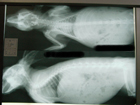

手術をした所。

あえて見にくく小さくアップ^^;

今回の手術を行う時に、どうせ全身麻酔をするならと思って

レントゲン撮影と血液検査をお願いしてありました。

レントゲンを見て先生は・・・

「太ってるんじゃね?」

だって・・・・・・〓■●ポテッ

レントゲン、嘘つかない!です。・・・〓■●ポテッ

レントゲン写真、なんか鳥みたいですよね(笑)

レントゲンは恐竜みたいですよね^^;

レントゲン!!とさかが映ってますわねん^m^

レントゲン写真って、なんか不思議な生物に見えるよね~(^^;

レントゲン。恐竜みたいだよねー(笑)